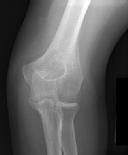

Figures 1 and 2 are the radiographs of a 35-year-old man who has elbow pain after falling from a ladder onto an outstretched hand. Examination reveals elbow pain, swelling, limited motion, and normal neurologic function.

A pathognomonic radiographic feature of this injury is a